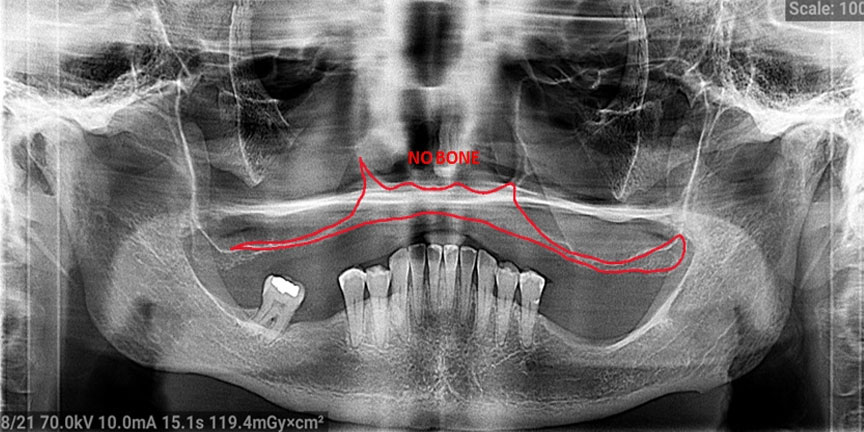

Severe Bone Loss